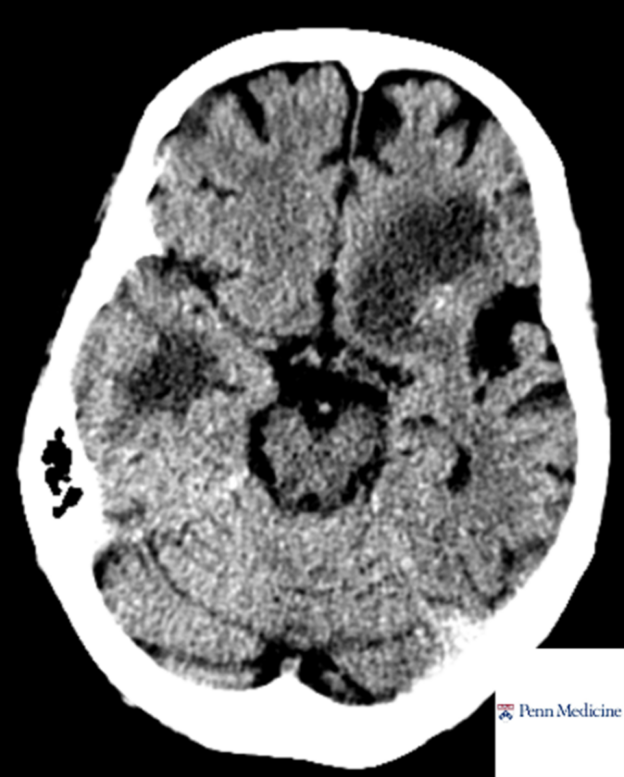

60-year-old woman with weight loss, fevers, confusion

A 60-year-old woman with history of treated pulmonary adenocarcinoma and renal and pancreas transplantation on chronic immunosuppression presents with progressive weight loss, fevers, and confusion.